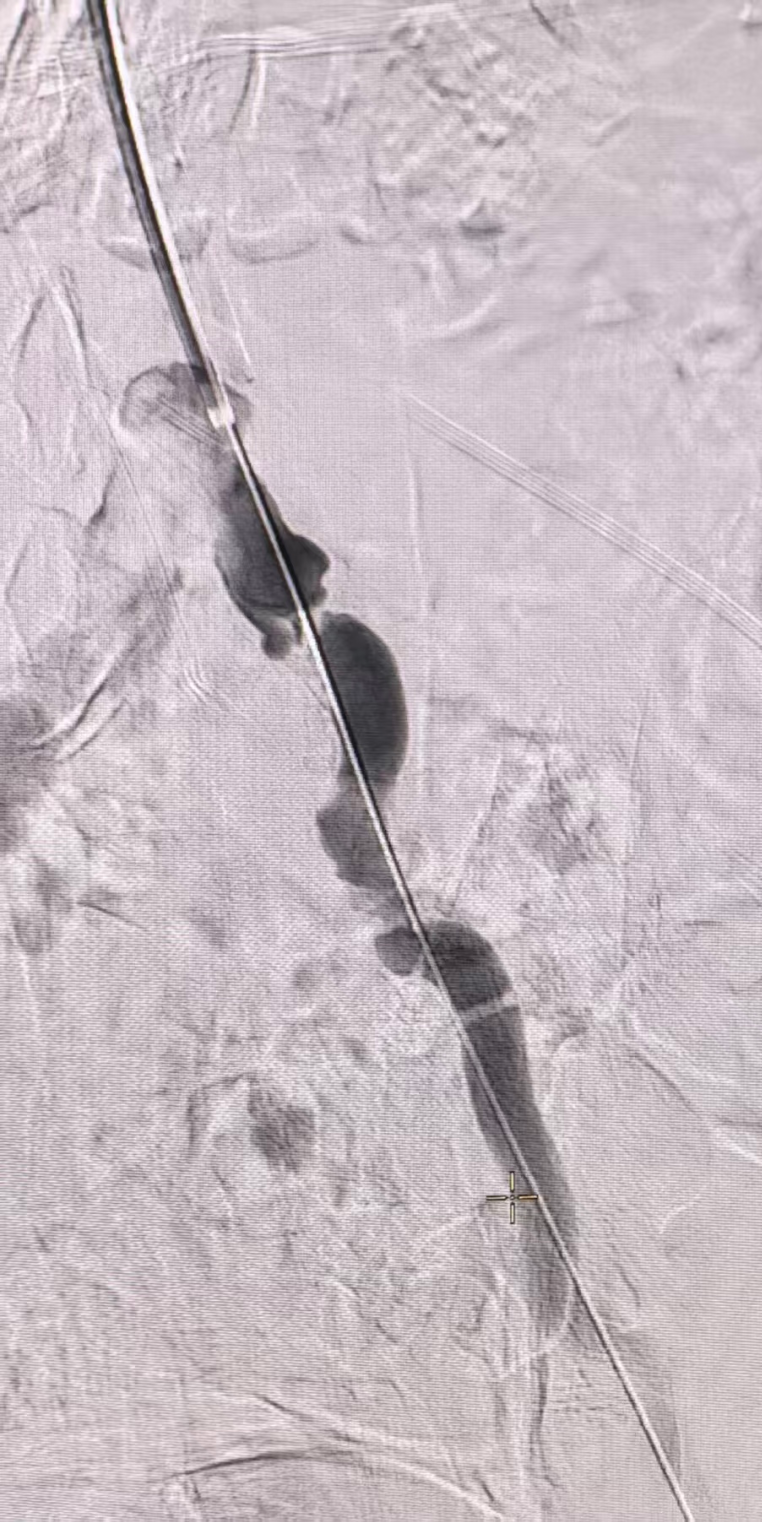

导丝导管配合经左锁骨下动脉选入降主动脉,造影见双肾动脉血流通畅,左髂总动脉局部重度狭窄,左髂外动脉及股腘动脉血流通畅。

动脉长鞘怎么置入桡胜一筹丨吴巍巍主任、赵俊来教授团队:应用Brite Tip RADIANZ长鞘经桡动脉治疗下肢动脉粥样硬化闭塞症一例_https://www.jmylbn.com_新闻资讯_第15张

动脉长鞘怎么置入桡胜一筹丨吴巍巍主任、赵俊来教授团队:应用Brite Tip RADIANZ长鞘经桡动脉治疗下肢动脉粥样硬化闭塞症一例_https://www.jmylbn.com_新闻资讯_第16张

2.沿导丝交换BRITE TIP RADIANZ™ 经桡导引长鞘。导丝导管配合通过左髂动脉病变,交换Supracore导丝,沿导丝进入球囊8-60行预扩张,复查造影仍可见残余狭窄。

动脉长鞘怎么置入桡胜一筹丨吴巍巍主任、赵俊来教授团队:应用Brite Tip RADIANZ长鞘经桡动脉治疗下肢动脉粥样硬化闭塞症一例_https://www.jmylbn.com_新闻资讯_第17张

置入经桡导引长鞘

动脉长鞘怎么置入桡胜一筹丨吴巍巍主任、赵俊来教授团队:应用Brite Tip RADIANZ长鞘经桡动脉治疗下肢动脉粥样硬化闭塞症一例_https://www.jmylbn.com_新闻资讯_第19张

8-60球囊扩张

3.沿导丝进入支架(8-80)精准释放于左髂动脉并完整覆盖病变,沿导丝进入球囊行支架内后扩张。复查造影见左髂动脉血流恢复,支架形态可,无明显残余狭窄或造影剂外溢。